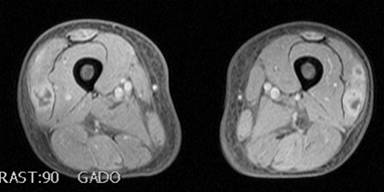

During the fourth cycle of chemotherapy, the patient reported persistent pain of both lower limbs causing major difficulties in mobilizing. The pain was described as crushing sensation and cramps localized to the anterior side of both thighs causing insomnia. Motor function, sensation and reflexes of lower limbs were normal. The skin had a paper-like texture in regard of the painful lesion. Biological markers were as follows: creatine kinase 1.6 N, lactate dehydrogenase 2.3 N and low levels of complement C3 and C4, with no evidence of inflammation. Doppler examination was unremarkable, hence excluding arterial or venous causes. MRI of lower limbs showed a diffuse T2 hyperintensity in both anterior muscles compartments associated with necrotic lesions (Figures 1 and 2), compatible with bilateral quadriceps polymyositis.

|

Figure 1. MRI (T1) axial section of both thighs with gadolinium injection. Necrotic aspect of both vastus lateral quadriceps. |